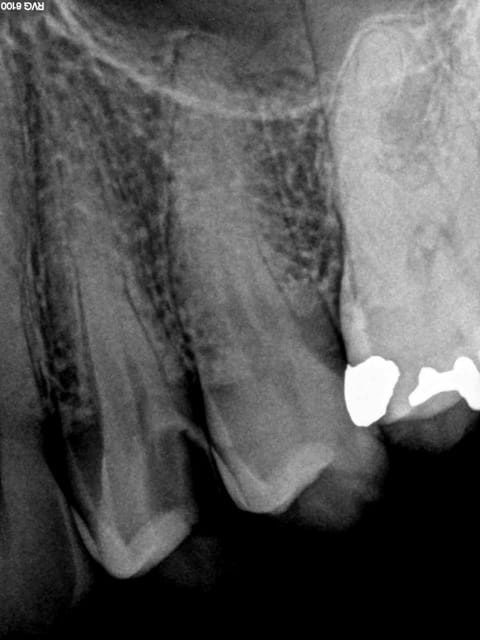

traitement endo réussi

D'après Laurichesse;la finalité de tout traitement endo est

de conserver sur l'arcade la dent dépulpée dans un état sain et fonctionnel(1986)

Standards de qualité endo ANDEM 1996

signes radios:espace desmodontal inf à 1mm

pas d'image apicale

lamina dura normal

pas de résorption apparente

obturation dense confinée à l'espace endo et

semblant atteindre la jonction cémento dentinaire(à un mm

de l'apex anatomique environ)

autrement quand je fais un RTE avec lésion apicale visible à la radio je me laisse environ 6 mois pour le contrôle de guérison

C'est un traitement conforme aux recommandations de la HAS. Celui ci n'est pas conforme : pourquoi ?

Et pourtant obturation à l'apex, thermo-compaction.